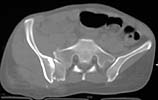

the enclosed ct image demonstrates her second, not upper sacral segment.

her plain pelvic radiographs indicate upper sacral dysmorphism, which has a significant impact on safe iliosacral screw insertion, regardless of imaging modality chosen to assist insertion.

the ct image reveals no significant posterior pelvic degloving injury, for that single axial image.

we need more ct info(images) to make appropriate therapeutic recommendations.

the strategy relies on the other images which reveal the exact iliac fracture-sacroiliac disruption sites, local soft tissue condition, as well as the upper sacral morphology.